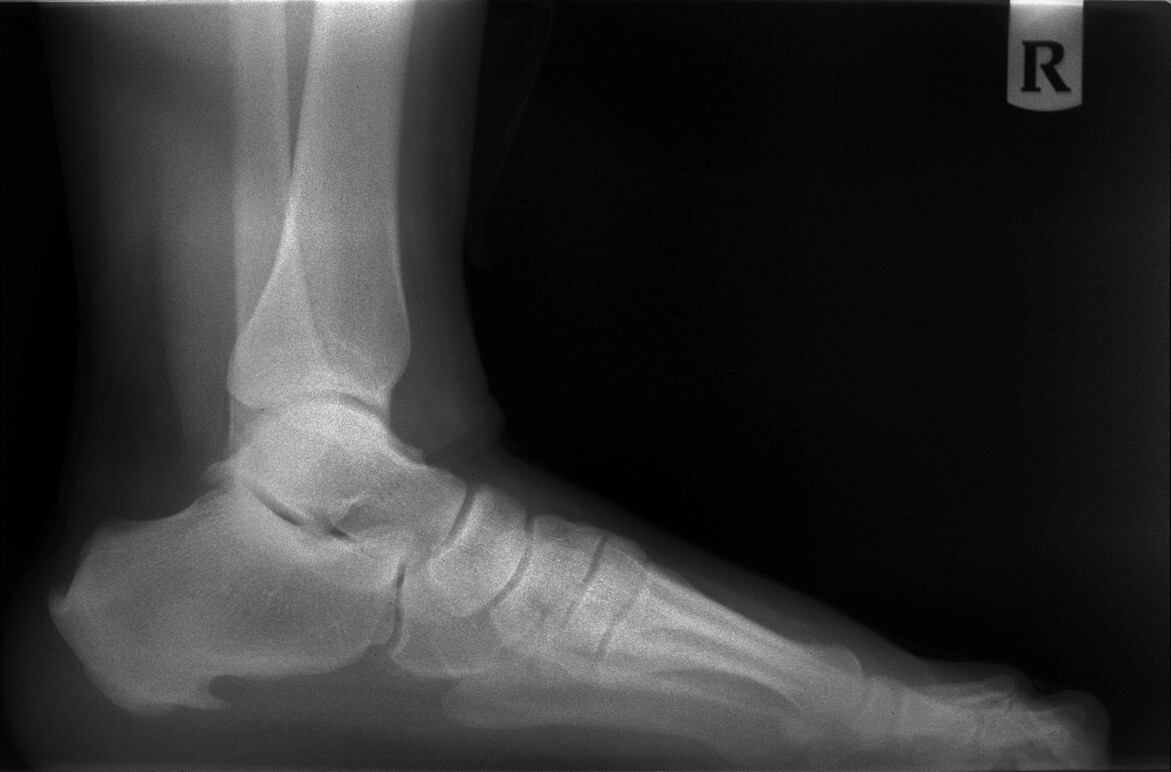

Heel Pain

Up to 15% of all foot complaints are related to heel pain.16 Plantar fasciitis is defined as inflammation of the plantar fascial tissue at the plantar aspect of the heel and is characterized by intense pain localized to the inferior portion of the calcaneus, most commonly along the plantar medial tuberosity. Any portion of the plantar fascia can be affected. The plantar fascia is a thick, broad, and dense band of longitudinally arranged collagen fibers that begins as an attachment to the anterior aspect of the calcaneal tuberosity.17 The plantar fascia is divided into three bands: medial, central, and lateral. Heel spur formation has been associated with the proximal plantar fascia, but the spur actually is deep to the plantar fascia and lies within the origin of the flexor digitorum brevis muscle. Most often, heel spurs exist without producing symptoms, although in some patients, heel spurs may become a source of symptoms.18 (See Figures 1 and 2.)

Figure 1. Image Showing Plantar and Posterior Spur

Figure 2. Image Showing Posterior Spur

Conventional plantar fasciitis is consistent in its initial presentation. Signs and symptoms include intense pain along the bottom of the heel with initial weight-bearing in the morning, commonly referred to as post-static dyskinesia.17 The pain typically subsides after a few steps, until the plantar fascia and plantar intrinsic muscles stretch out, but the pain frequently progresses throughout the day with prolonged weight-bearing. In severe cases, associated signs and symptoms include heel edema and thickening of the plantar heel pad. Plantar fasciitis can progress to complete or partial rupture of the plantar fascia. Chronic or recalcitrant plantar fasciitis may be confused with plantar fasciosis, which is a natural thickening and age-related degenerative process of the plantar fascia.